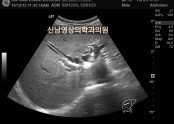

• 췌장에 혹, 간 낭종, 상복부 초음파

• 등록일 2025-12-01 07:38:59

•  복부는 배를 말하는 의학용어입니다.의학용어는 쉬운 말도 어렵게 하지요?상복부라는 뜻은 바꿔 말하면 배의 윗부분을 말하는 것입니다.하복부는 배의 아랫부분이 되겠지요. 왜 복부를 상,하로 나눴을까요?상부에는 간, 쓸개, 췌장, 비장, 신장이라는 장기가 위치해…